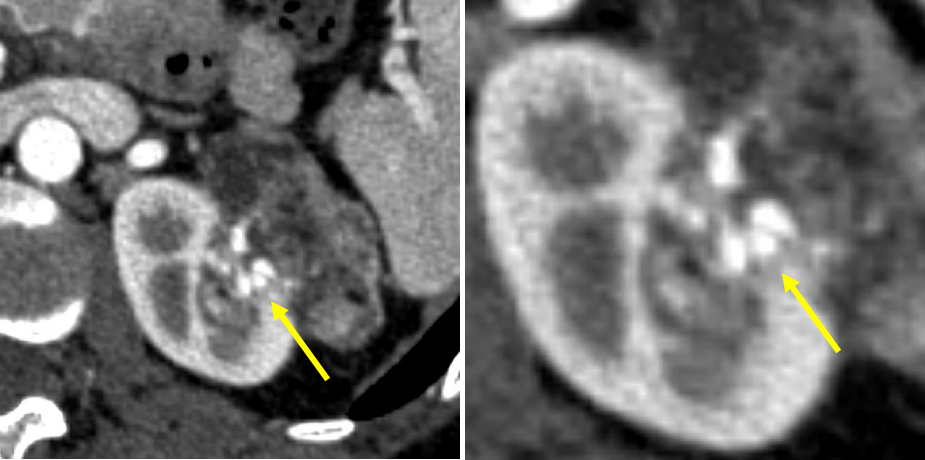

本症例では術前の造影CTから左腎動脈上極枝のほか、左腎動脈本幹から分岐する左上腎被膜動脈が栄養血管として同定され、この画像情報を参考にして塞栓術が施行された。術中の血管造影においても左上腎被膜動脈が腫瘍を栄養する血管として確認され、術前の造影CT所見の通りであった。

この早期動脈相は術前の腎動脈解剖を詳細に把握するために最も重要な撮影時相である。薄層スライス厚での撮影により、高精細なMPR(多断面再構成)、MIP(最大値投影法)による3D画像処理が可能となり、腎動脈の起始部から末梢分枝まで、さらに異所性分岐などの解剖学的バリエーションも明瞭に描出できる。特に塞栓術においては、標的血管の同定と周囲血管との関係性の把握が重要であり、これらの三次元的な血管構築の評価は手技の成功に直結する。このようにbolus tracking法を用いた精密なタイミング制御と高分解能撮影の組み合わせにより、塞栓術の安全かつ確実な施行に必要な血管解剖情報を包括的に取得している。